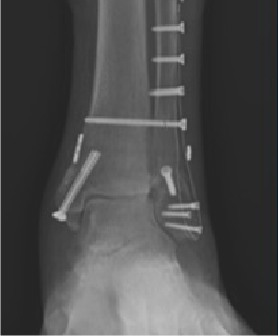

Surgical technique in these cases varied based on surgeon, pathology, approach, and procedures performed. This variation includes joint preparation technique for arthrodesis procedures, type of internal or external hardware, and fixation methods. However, NHBGS was the only adjunctive material used for all patients in the study with no additional grafts, graft substitutes, or any other biologics added. Available quantities of the NHBGS included 5mL or 10mL, with two different delivery methods (Figure 1), quick delivery (QD) and superior bone matrix (SBX) (Figures 2A-B). One advantage of the silica-based medium is the ease of handling. Surgeons can mold, shape, and contour the material while maintaining structure (Figure 3). Some examples of the NHBGS application included tibiotalocalcaneal fusion using a custom-printed metal scaffold (Figure 4A-B), tarsometatarsal arthrodesis (Figures 5A-B), and ankle fracture open reduction with internal fixation (Figure 6).